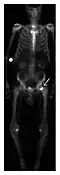

Proximal femoral fractures usually occur in osteoporotic patients, and their signs include subtle neck angulation, trabecular angulation, and subcapital impaction line. A frog-leg lateral view may be helpful if the greater trochanter is short enough. However, positioning can be difficult because of hip pain. In patients with strong suspicion of proximal femoral fracture and negative radiographs, MRI limited to coronal T1 W images and scintigraphy can be highly valuable (Figures 13 and 14). Such an option, with limited examination time, is cost-effective and allows reliable exclusion or confirmation of the diagnosis, preventing an unnecessary stay at the hospital or delayed treatment. Moreover, MRI helps to detect soft tissue abnormalities which are more frequently seen in femoral, acetabular, and pubic injuries than sacral lesions. Concomitant fractures are also frequently seen in typical pelvic sites.[1]

a

b

Figure 14: Subcapital insufficiency fracture in a 55-year-old man with a left hip pain without a history of trauma. Anteroposterior and Lauenstein view radiographs centered on the left hip do not show an obvious fracture line, but mild acetabular osteophytosis was noted consistent with hip osteoarthritis (not shown). (a) Coronal T1-weighted MRI shows a linear low-signal band through the femoral neck corresponding to a fracture line (arrowheads). (b) Bone scintigraphy shows focal uptake (arrow) corresponding to the fracture.[1]